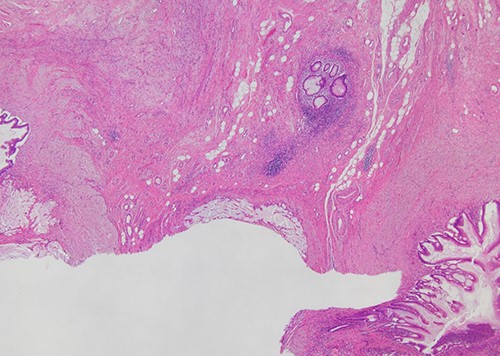

Macroscopic examination of the specimen disclosed the presence of a duplicated appendix, which had partial duplication with both appendices sharing a common dilated base, like ‘Y-shaped’, measuring 1.5 cm on a single caecum (Fig. 5). Microscopic examination showed replacement of the normal appendiceal epithelium by mucin-producing columnar glandular epithelium with low-grade dysplasia from the common base to both duplicated appendices (Fig. 6). There were no histological findings of conventional, high-grade mucinous appendiceal adenocarcinoma, such as the proliferation of mucinous epithelial cells with high-grade dysplasia, architectural complexity, cribriform pattern or glands infiltrating in a desmoplastic stroma. The pathological diagnosis was a LAMN with pTis (LAMN) pN0 stage 0, using pTNM, Eighth Edition of AJCC, with free surgical margins and on the duplicate appendix. A follow-up CT was performed 6 months after the surgery, reporting no evidence of distant metastasis or pseudomyxoma peritonei (PMP) which is the clinical term for the spread of LAMN to the peritoneal cavity.

Histopathological examination (H&E stain; ×40 magnification) showing that mucin-producing columnar glandular epithelium with low-grade dysplasia replaced the normal appendiceal epithelium from the common base to both of duplicated appendices.